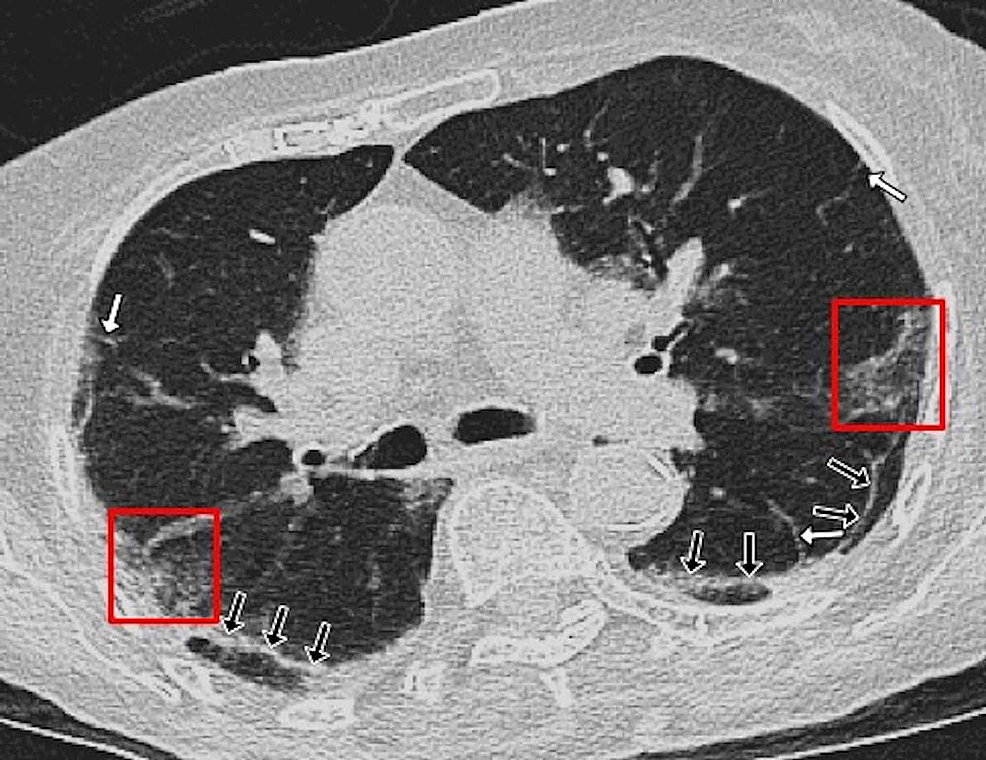

In the CT images, GGO plus consolidation was observed bilaterally in all 18 (100%) patients. No pure GGO or pure consolidation was encountered in our cohort. The predominant shape was amorphous (72%). Lesions showed no specific lobar predilection, but most lesions were localized posteriorly and peripherally.

The distinctive CT features in our cohort are summarized in Table 3, including GGO and consolidative patchy mostly amorphous (72%) lesions, bilateral posterior and peripheral multi-lobar lung involvement, pleural effusions, subpleural fibrotic lines, subpleural sparing, vascular engorgement, occasional crazy paving, occasional mediastinal lymphadenopathy, pleural thickening, lack of cavitation, and absence of reverse halo (atoll) signs.

Subpleural sparing, which was observed in this patient cohort, has never been reported before, whereas mediastinal lymphadenopathy has been reported occasionally in the literature in English [11]. Focal vascular engorgement, septal thickening, and a subpleural fibrotic line were seen frequently in our cohort, with frequencies of 83%, 72%, and 61%, respectively.

Patients’ CT features are presented in detail in Figures 3, 4, 5, 6, 7, 8. A majority of cases (56%) had moderate severity scores. There was no correlation between the severity score and mortality, p=0.790 (Table 4).